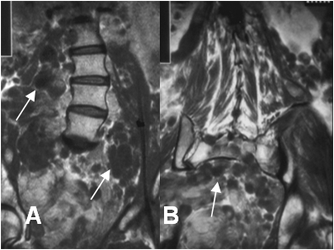

Fig 179 B. Neurofibromas múltiples.

A y B: RM coronal en T1. Múltiples imágenes ovaladas y de bordes bien definidos,

que corresponden a neurofibromas.